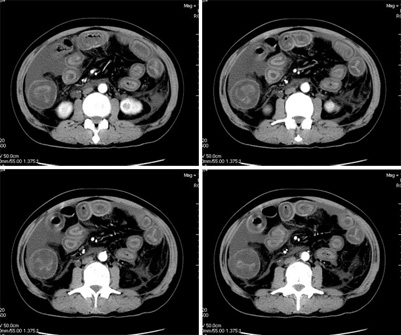

增强

我们仔细看了三期增强的动静脉血管,未看见血栓的形成,因为三期的片子太多有168张,无法全部上传,在动脉期及静脉期看到下腔静脉及门静脉内密度不均匀在平衡期均显示均匀,所以不考虑血栓形成引起的回流障碍.刚才老公在电脑边走过(他是外行),发表意见说这人是不是吃了什么东西引起肠子中毒.我想了一下似乎有道理,但是是什么东西会引起这样的改变,并且从病程上来看有一个多月的病史,又不是急性发作,网上高手们给予指点,如需要更多的另两期的图片,我将上传.

肠管壁增厚,以升结肠、横结肠明显,肠袋变浅,cta显示肠系膜上动、静脉显影清楚,管腔未见狭窄,同时大量腹水,考虑:肠麻痹水肿?食物中毒?

本例ct表现是肠道的整体性充血、水肿,以结肠特别是横结肠、升结肠、盲肠为显著,横结肠一眼粗略看过去,极似极度水肿之胰腺。回肠末段亦呈明显近似结肠改变,小肠则以充血为主,水肿相对轻微。诸段肠管无明显如溃疡、出血等局部损害,重度腹水。肝脏体积变小,肝裂增宽,以肝圆韧带为明显。肝脏各部比例尚正常,无局部外突或内凹,密度均匀一致。胆囊增大,所给图片及楼主已经仔细观察过,肝段下腔静脉肠系膜静脉均正常。

患者病史已经一个多月了,现在小肠以充血为主,水肿相对轻微。而大肠却以水肿为主,充血相对轻微。同时,回肠末段、盲肠、升结肠及横结肠表现明显,是不是可以这样理解:患者是某种食物或药物急性轻度中毒或慢性中毒,现在致病因素已经下行至回肠末段、盲肠、升结肠及横结肠,并将继续逐步下移。而该处肠管的表现既有毒素直接吸收、刺激所致,又有局部过敏反应所致。那么,腹腔积液将理解为肠壁渗出液堆积(不支持点:肠管外壁光整,周围无液体聚集,所以此推理可能性较小)。这样看来,在积极治疗下,病人恐怕会逐渐康复的。